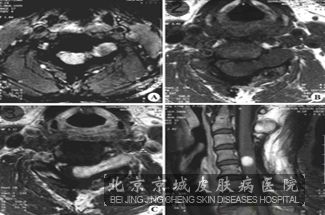

北京京城皮肤医院介绍讲:神经纤维瘤的神经症状主要就是表现为颅内肿瘤、椎管内肿瘤、周围神经肿瘤。其中周围神经肿瘤的周围神经均可累及,肿瘤议案一般呈串珠状沿神经干分布,一般没有明显的症状表现,如果有突然长大或剧烈疼痛的现象,说明可能为恶变迹象。